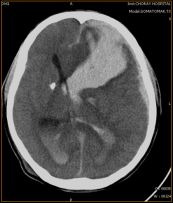

Xuất huyết não thất được coi như một hiện tượng thứ phát do chảy máu não vỡ hoặc chảy máu nhu mô não vào khoang não thất. Đây là một trong những bệnh lý gây tử vong cao. Chẩn đoán và điều trị sớm bệnh sẽ giúp nâng cao cơ hội sống cho bệnh nhân. Để hiểu rõ hơn về hội chứng nguy hiểm này, mời các bạn tham khảo bài viết dưới đây!

Xuất huyết nhân bèo trái là một trong những bệnh lý rất nguy hiểm. Để hiểu rõ hơn mời các bạn cùng tham khảo bài viết ngay dưới đây nhé!